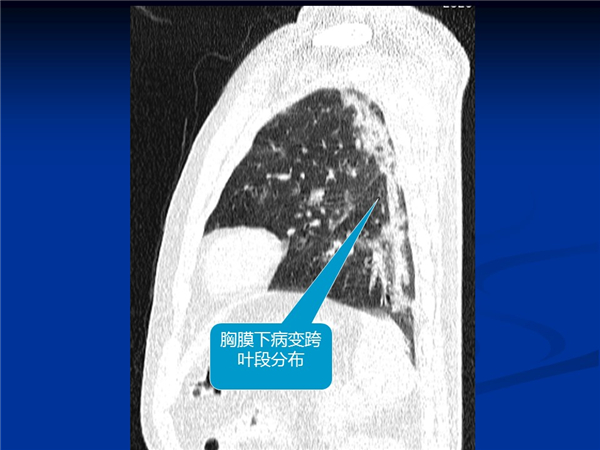

【病例分享】新型冠狀病毒感染肺部CT影像4例(常德市第一人民醫(yī)院)